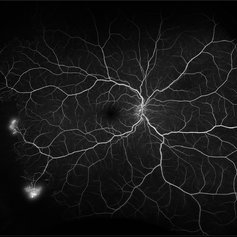

Sickle cell retinopathy (Proliferative) (2 files)

Sickle cell retinopathy (Proliferative) (2 files)

Proliferative sickle retinopathy (1 file)

Proliferative sickle retinopathy (1 file)

Proliferative Sickle Cell Retinopathy (Stage3) (10 files)

Proliferative Sickle Cell Retinopathy (Stage3) (10 files)